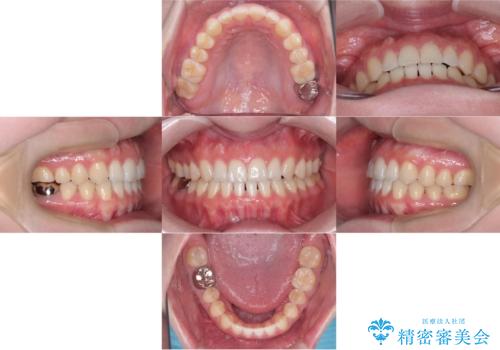

すきっ歯・切端咬合・空隙歯列|インビザラインで11ヵ月で治療完了

- すきっ歯と切端咬合(上下の前歯が先端で当たるかみ合わせ)を主訴にご来院された患者様です。

矯正検査を行った結果、非抜歯でインビザラインによる治療が可能と判断し、マウスピース矯正で改善を行いました。

11ヵ月で矯正治療が終了し、前歯の隙間も改善、見た目とかみ合わせも良好な状態となり、患者様にも大変ご満足いただけました。